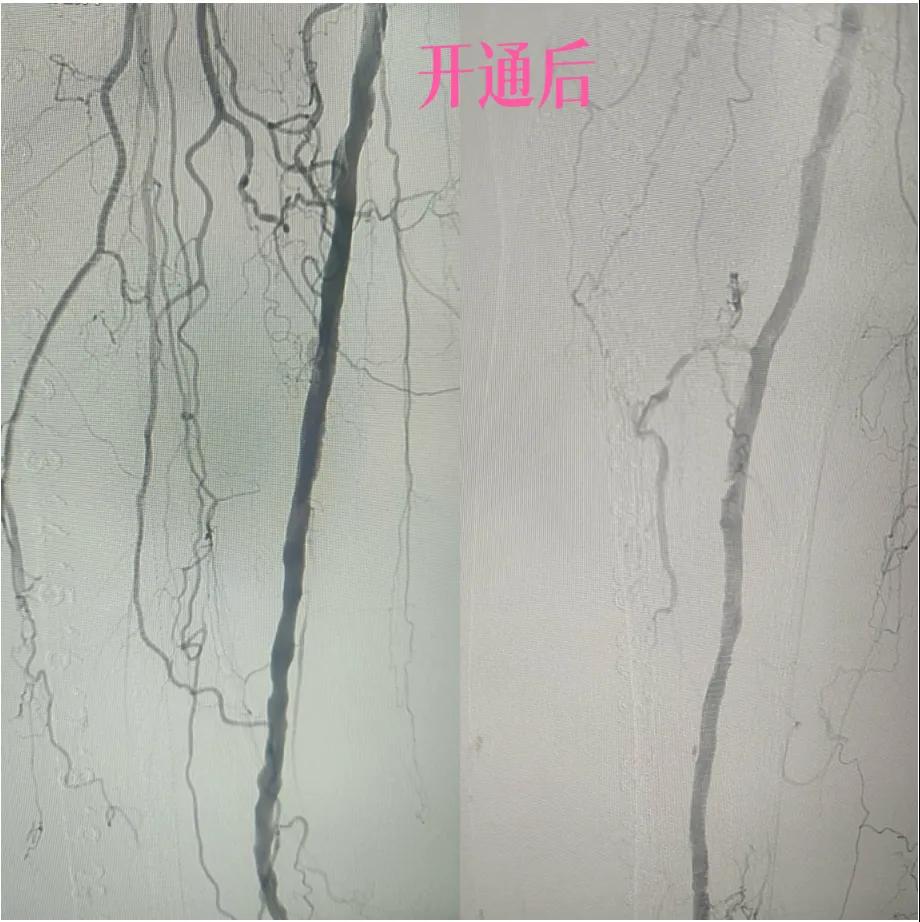

近日,漯河市中醫(yī)院外二科血管外科介入團隊利用微創(chuàng)介入技術(shù)成功保住一患者患肢。

據(jù)悉,患者以“右足足趾疼痛伴第三足趾壞疽4月余”為主訴來院就診,查體患者右足第三趾末端呈壞疽狀,已結(jié)痂,足趾根部及足背部紅胖、壓痛,右側(cè)足背動脈,脛后動脈搏動未觸及,下肢深靜脈血管彩超:雙側(cè)下肢深動脈粥樣斑塊形成,右側(cè)腘動脈流速減低,右側(cè)脛后動脈及足背動脈不顯示(閉塞?)

為了挽救患者的患肢,避免截肢,外二科血管外科介入團隊經(jīng)過縝密的術(shù)前討論和評估,決定采用目前微創(chuàng)介入技術(shù)——下肢動脈藥涂球囊擴張成形術(shù)(DCB)。

2.  “探路”與“疏通”:在先進的DSA(數(shù)字減影血管造影)設備實時引導下,猶如擁有了“透視眼”,導管導絲巧妙穿越病變血管的狹窄、閉塞段。這需要極高的技巧和對血管解剖的深刻理解。

4.  即刻“見證”:再次造影顯示,原本狹窄閉塞的血管段血流恢復通暢!足部遠端血管顯影較前明顯改善。手術(shù)過程順利,患者靜息痛較前明顯改善。